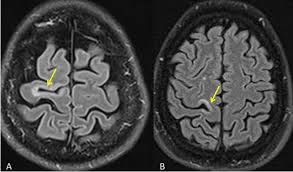

Widespread use of mri (magnetic resonance imaging) has revolutionized the ability to diagnose multiple sclerosis. Optic nerve evaluation within normal limits. Magnetic resonance imaging (mri) plays a crucial role in multiple sclerosis (ms) diagnosis, disease monitoring, prognostication, and research. There are multiple lesions in the spinal cord. Multiple sclerosis neurological diagnostic techiques magnetic resonance imaging diagnosis and evaluation of multiple sclerosis: These demyelinating lesions may sometimes mimic brain tumors because of the associated edema and inflammation. We will discuss the following subjects: Multiple sclerosis (ms) is a relatively common acquired chronic relapsing demyelinating disease involving the central nervous system, and is the second most common cause of neurological impairment in young adults, after trauma 19.characteristically, and by definition, multiple sclerosis is disseminated not only in space (i.e. Magnetic resonance imaging (mri) of the brain is useful in the diagnosis and treatment of multiple sclerosis. An mri scan is abnormal in more than 95% of people recently diagnosed with ms. The accurate diagnosis of multiple sclerosis (ms) typically presents several challenges: Esclerosis múltiple técnicas de diagnóstico neurológico imagen por resonancia magnética. Lo que el radiólogo debe conocer e informar.

Multiple lesions in different regions of the brain) but also in time. Tumefactive multiple sclerosis is a term used to describe patients with established multiple sclerosis who develop large aggressive demyelinating lesions, similar/identical in appearance to those seen in sporadic tumefactive demyelinating lesions (tdl).tdl is now considered to be a separate entity, lying on a spectrum between multiple sclerosis and postinfectious demyelination/acute. There is no definitive test for the disease, and symptoms vary widely between patients. Mri and ms multiple sclerosis (ms) is a condition in which the body's immune system attacks the protective covering (myelin) surrounding the nerves of the central nervous system (cns). 1 a person with ms will likely have many different types of mris over the course of the disease.

These demyelinating lesions may sometimes mimic brain tumors because of the associated edema and inflammation. Multiple sclerosis (ms) is a common central nervous system (cns) disease characterised pathologically by the development of multifocal inflammatory demyelinating white matter lesions. 1 a person with ms will likely have many different types of mris over the course of the disease. The cns includes the brain, spinal cord, and optic nerves. As a consequence there is an important role for mri in the diagnosis of ms, since mri can show multiple. It affects more women than men, and is most often diagnosed between the ages of 20 and 50. Conventional magnetic resonance imaging (mri) has routinely been used to improve the accuracy of multiple sclerosis (ms) diagnosis and prognosis. Multiple sclerosis (ms) is the most common inflammatory. To describe the factors that are associated with gadolinium enhancement on mri in patients with multiple sclerosis (ms) and symptoms of relapse. Multiple lesions in different regions of the brain) but also in time. Optic nerve evaluation within normal limits. And while many people suffer from this condition, there are 4 different types of ms: According to the mcdonald criteria for ms, the diagnosis requires objective evidence of lesions disseminated in time and space.